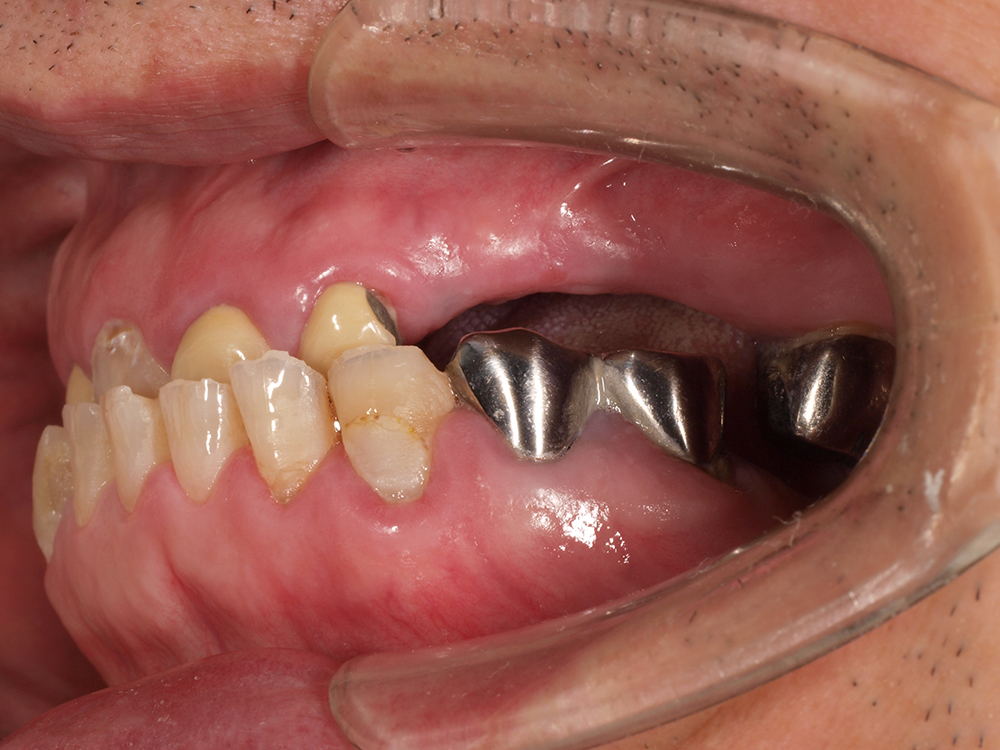

58歳 男性 歯科医療関係者紹介

- 主訴

- 右下を抜歯して噛めない

- 処置内容

- インプラント2本埋入

- 治療費用

- 約80万円(税込)

- 治療期間

-

8か月

仮歯完成まで5か月(この時点で噛めます)、+3か月で最終素材へ

- リスク

- 上部構造物、仮歯の破折、術後の腫れ(3日)、人工歯根脱落リスクがあります